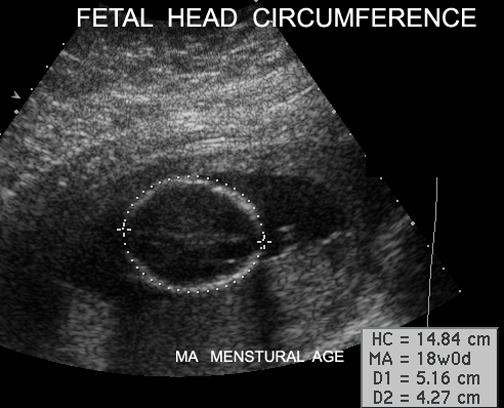

Fetal Head Circumference |